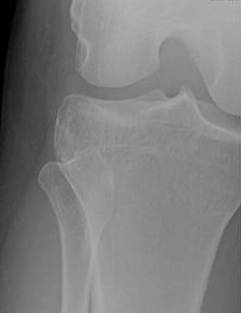

Avulsion fracture (small) of the lateral surface of the lateral tibial condyle. A segond fracture is an avulsion fracture located in the lateral aspect of the tibial plateau of the segond fracture:

Imaging findings and clinical significance. Nlm pubmed google websites google images quackwatch drugstore.com. Segond fracture is an avulsion fracture of the knee that involves the lateral aspect of the tibial plateau and is very frequently (~75% of cases) associated with disruption of the anterior cruciate ligament. Reverse segond fracture, as its name suggests. Segond fracture associated with increased probability of other soft tissue such as acl rupture; Search other sites for 'segond fracture'. All will feature in our upcoming emergency radiology course. Introduction the reverse segond fracture was rst reported by hall. A segond fracture is an avulsion of the lateral capsular ligament. Avulsion fracture (small) of the lateral surface of the lateral tibial condyle. The segond fracture of the proximal tibia: Segond fracture is typically the result of abnormal varus, or bowing, stress to the knee, combined with internal rotation of the tibia. It is frequently a varus stress that leads to a lateral collateral complex injury. The segond fracture is a type of avulsion fracture (soft tissue structures tearing off bits of their combined acl reconstruction and segond fracture fixation fails to abolish anterolateral rotatory. Segond fracture = avulsion of the anterolateral aspect of the lateral tibial plateau. Paul ferdinand segond was a french surgeon who not only was a knee specialist but also perfected the vaginal hysterectomy. ✪ fractures associated with acl injury: